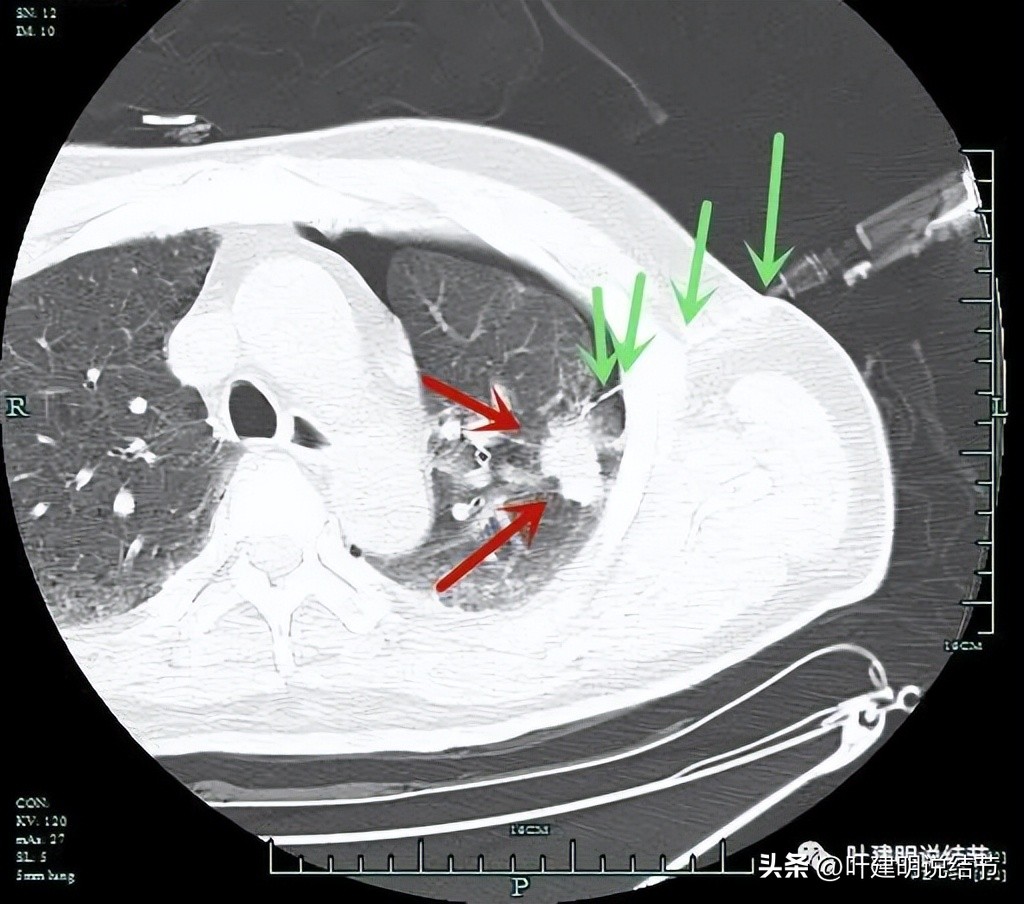

肺穿刺:红色箭头示病灶;绿色示穿刺针。

穿刺致气胸。

穿刺未能确诊。